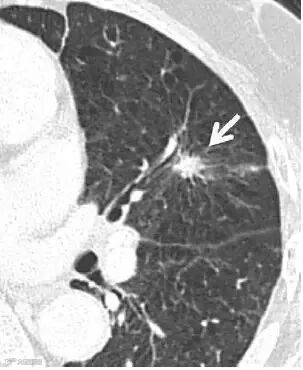

上图为可疑的实性毛刺结节,建议密切随访。